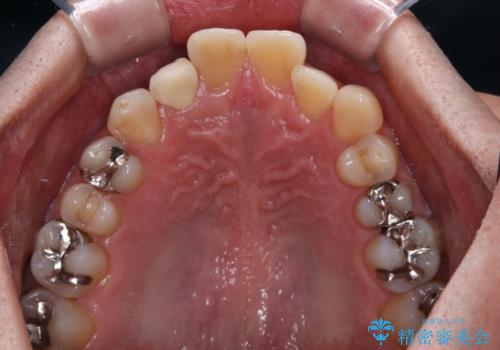

内側に倒れているため、下顎と強く干渉することが懸念されましたが、無理のない咬み合わせで、形態も左右対称に近い状態で仕上げることができました。